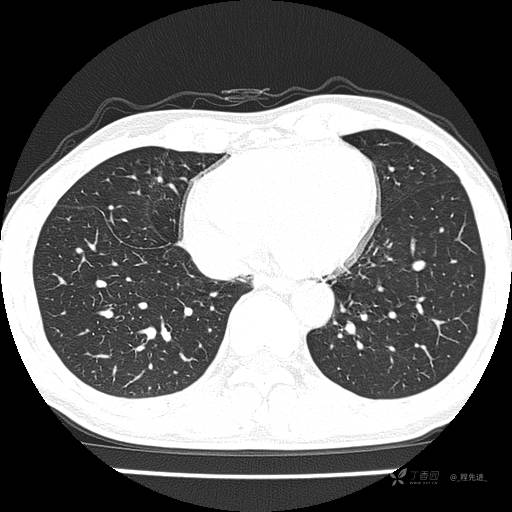

2月特别精彩病例|咳嗽、咳痰20余天,典型病例分享【结果已公布】

患者年龄:51岁

主诉:咳嗽、咳痰20余天

简要病史:20余天前开始出现咳嗽、咳痰症状,阵发性刺激性咳,白色粘痰,不易咳出,无发热,无咯血,无恶心、呕吐等不适,未诊治,咳嗽、咳痰症状持续存在。

体格检查:T:36.3 ℃ P:79 次/分 R:20 次/分 BP:128/64 mmHg,神志清楚,呼吸平稳,双肺呼吸音粗,右下肺闻及细湿性啰音。心率79次/分,节律整齐,各瓣膜听诊区未闻及病理性杂音。腹部未见异常,双下肢无水肿。

辅助检查:我院门诊胸部CT示:如下。心电图:窦性心律;正常心电图。